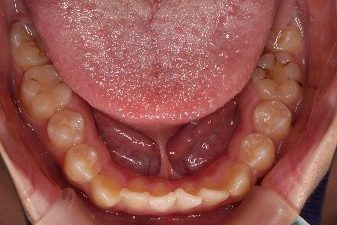

A1、舌小帯とは舌の下にある膜状のひだのことを指します。舌小帯が短く、舌の先端側に付着して、上手く舌を動かせない状態を舌小帯異常(舌小帯短縮症)といいます。

見た目の状態として

- 舌突出時に舌戦が小帯に引っ張られハート状にくぼむ

- 開校した状態で舌尖部が上方に上がらず顎につかない

などの症状があります。